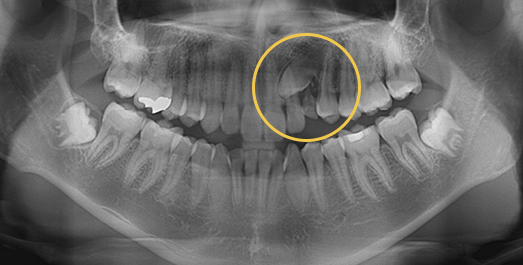

Impacted Tooth Solution

An impacted tooth remaining within the alveolar bone can cause damage to adjacent teeth.

Orthodontic traction is used to guide the impacted tooth into its correct position,

allowing it to erupt and seat normally within the dental arch.

BEFORE: 2011.08.12

AFTER: 2013.07.08

Side effects such as root resorption and gingival recession may occur.